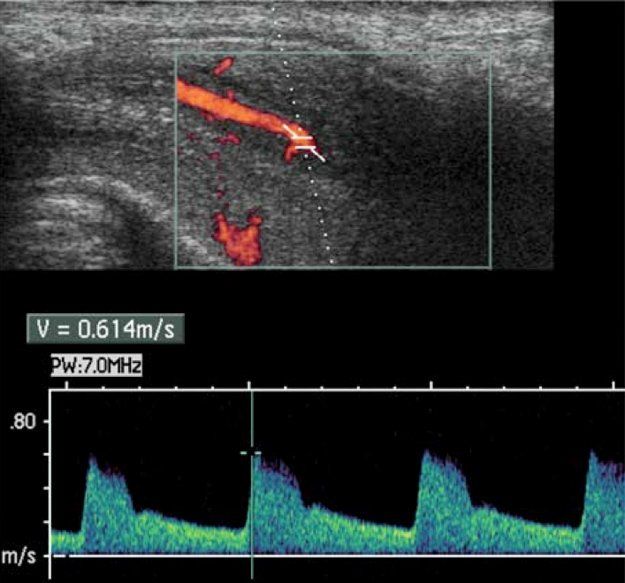

- Ecografia Andrologica con Ecocolordoppler